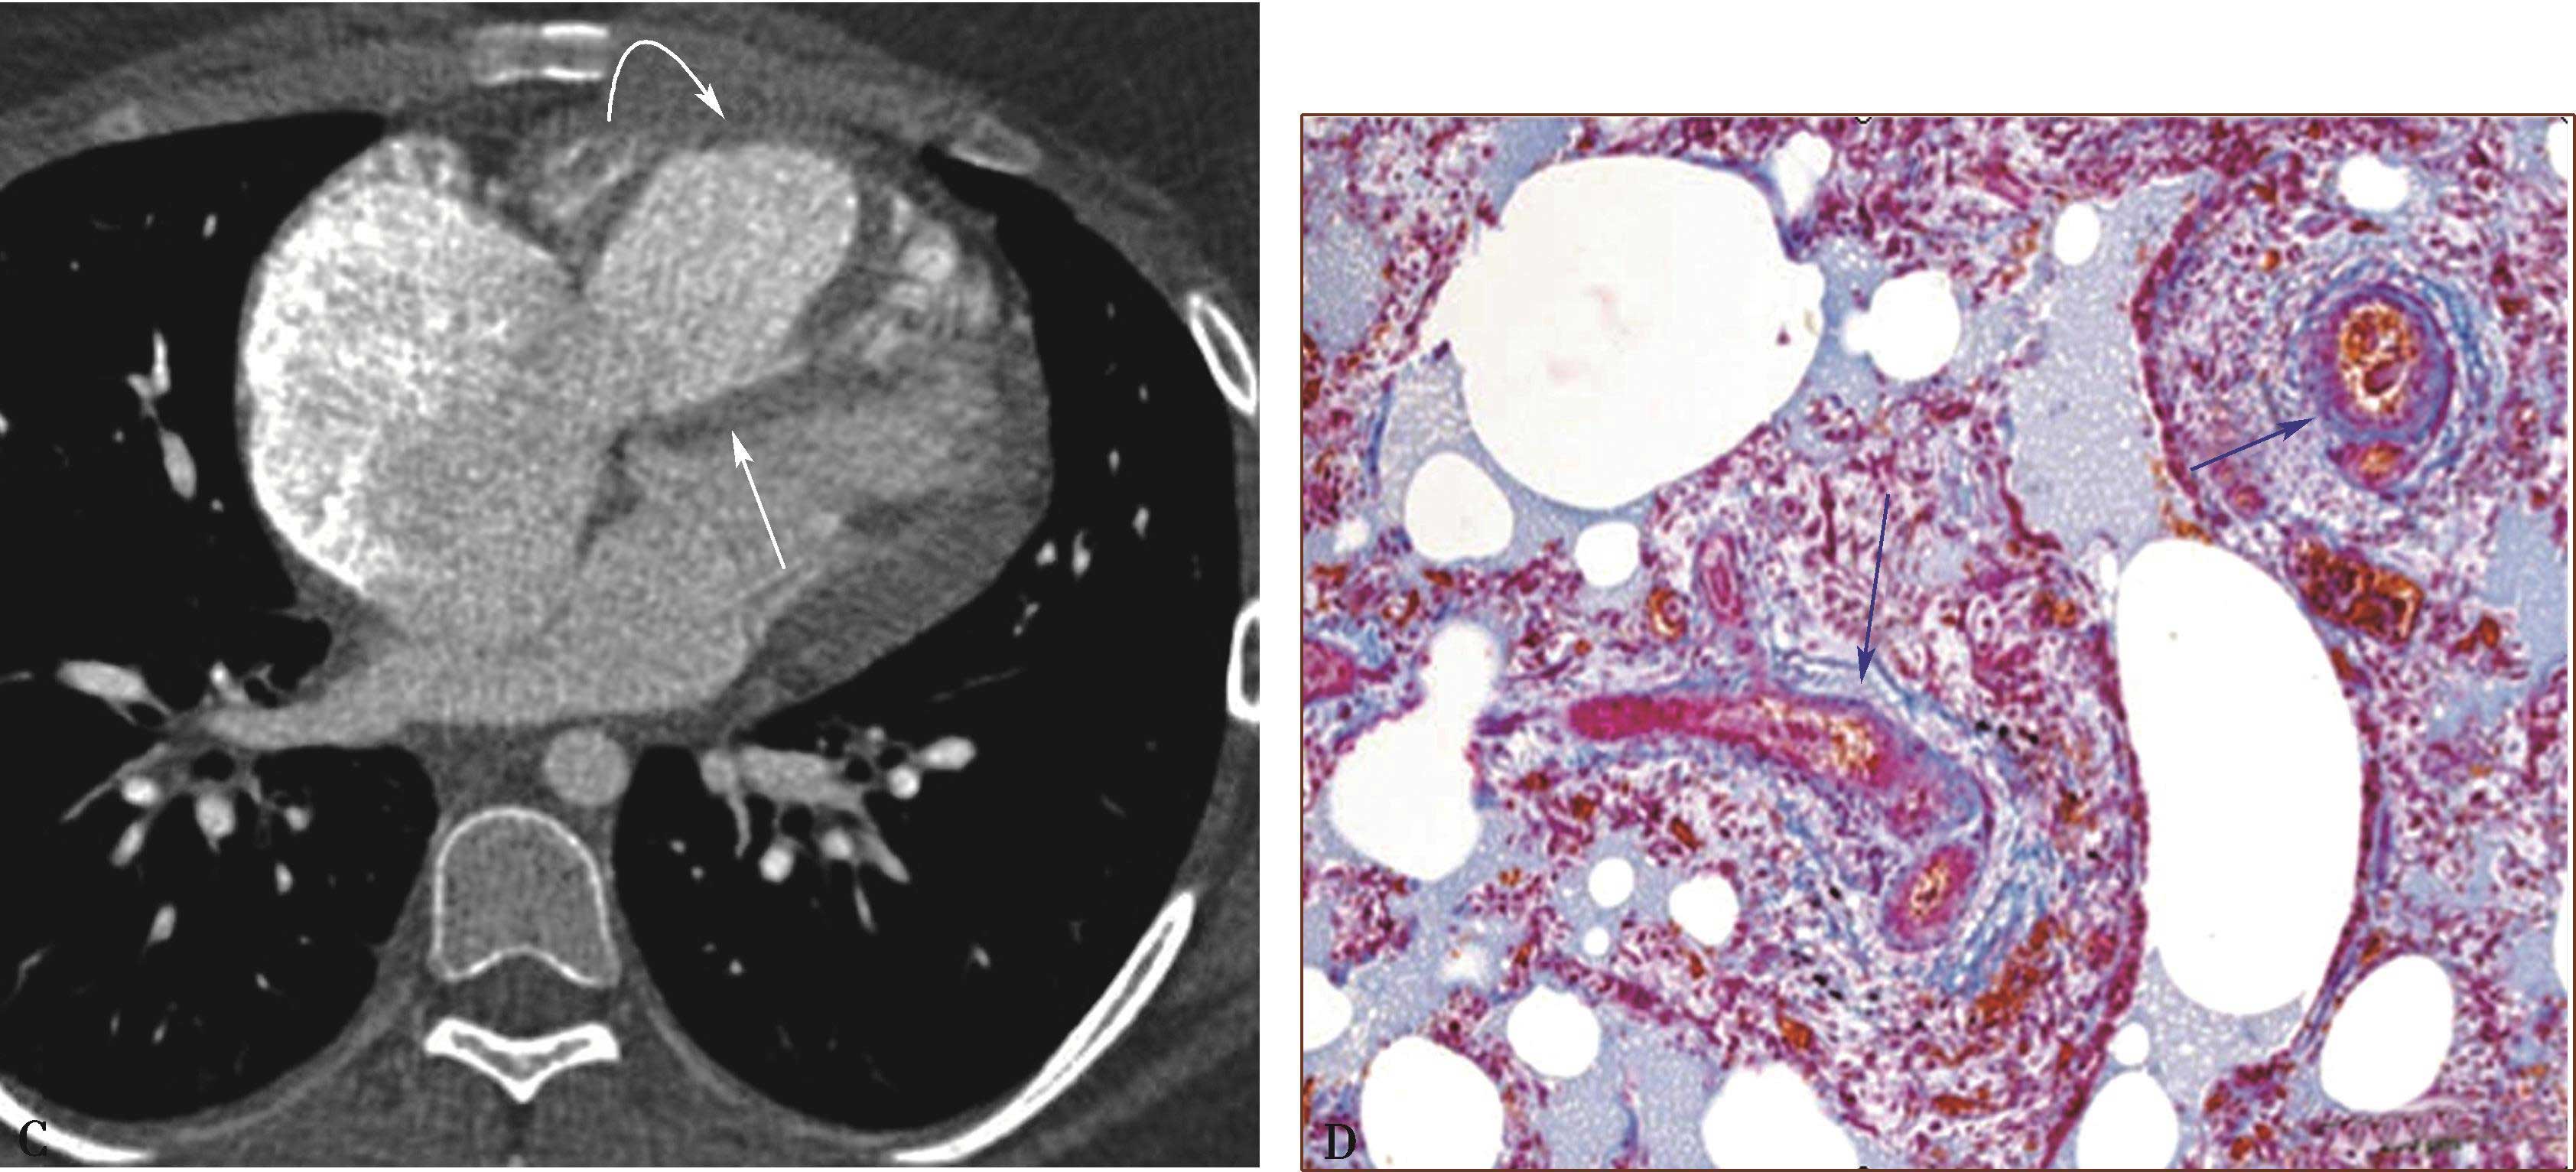

图8-10-3 PVOD女,17岁,喘憋,病理诊断:肺静脉阻塞病

A.CT冠状位重建(肺窗)显示广泛小叶间隔线和弥漫的边缘不清的磨玻璃结节影(箭头);B.右肺组织标本大体照显示间隔线增厚(曲箭头),边缘不清的淡红棕色实质结节灶(直箭头);C.横断图像(纵隔窗)显示右心房、右心室明显增大,右心室前壁增厚(弯箭头),室间隔平直(↑);D.右心房、右心室病理镜下所见小静脉阻塞(↑)